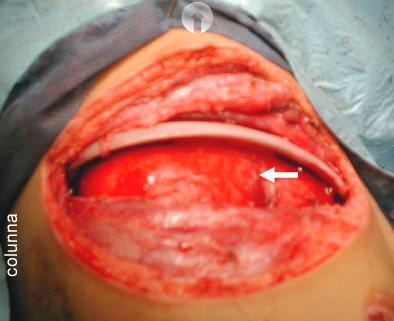

Foto A -

(Cabeza del paciente flecha en circulo)

- Flecha blanca:

El pulmon derecho parcialmente colapsado deja notar la presencia de fibrosis y material fibrino purulento en su superficie, debemos practicar tambien decorticación pleural para lograr re-expansion pulmonar.